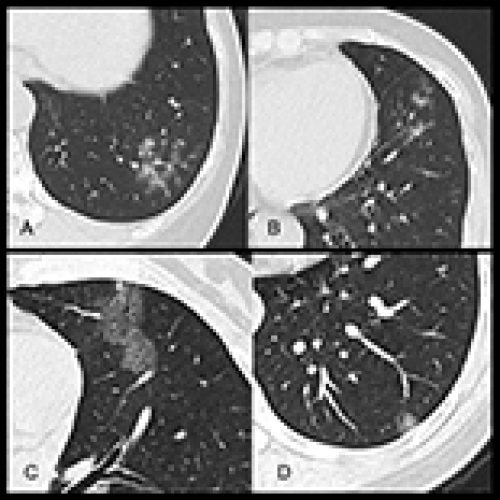

14 Nov 2021 : Clinical Research

Clinical Features and Temporal Lung Radiographic Changes in 25 Patients Recovering from COVID-19 Pneumonia: A Retrospective Case-Control Study

Chao Hu, Jian Ping Zeng, Ke Peng, Hong Xia, Huan Ming Zhang, Zhi Zhong, Ming Yan Jiang

3,640 973 0